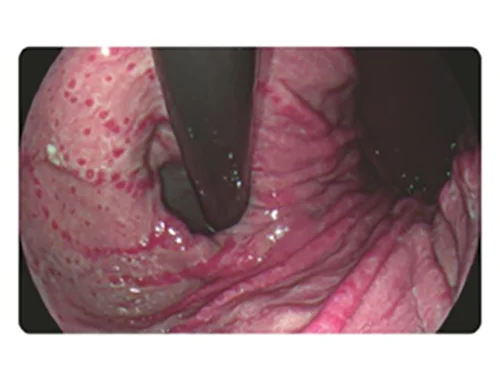

Белый свет

DSI

Белый свет

PSI

Белый свет

TEI